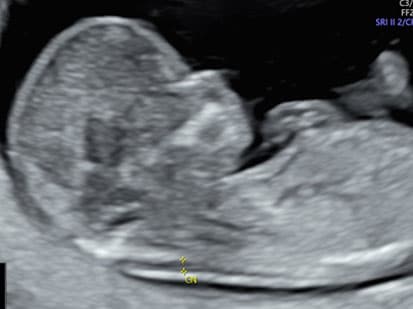

3. L’échographie du 2ᵉ trimestre (22 à 23 SA – 4mois 1/2)

Souvent appelée échographie morphologique, elle est dédiée à l’étude détaillée de l’anatomie fœtale.

Elle permet :

• D’examiner tous les organes du bébé : cerveau, cœur, reins, estomac, membres, colonne vertébrale, etc.

• D’évaluer la croissance et le bien-être fœtal

• De repérer certaines malformations si elles sont présentes

• De contrôler la position du placenta et la quantité de liquide amniotique

C’est aussi, si vous le souhaitez, le moment de découvrir le sexe du bébé.

Selon la position du bébé, nous vous proposons une échographie en 3D.